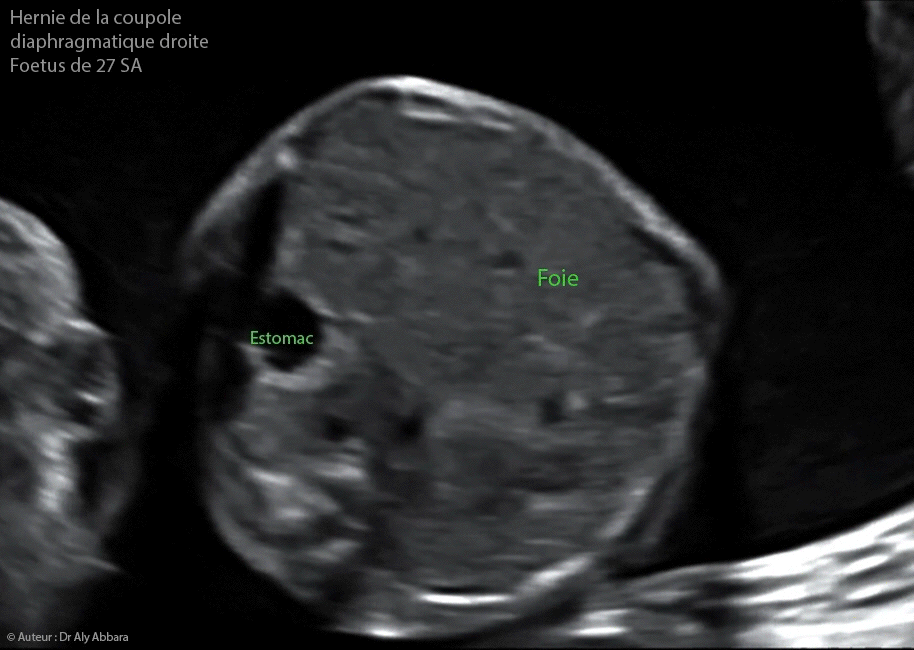

Images échographiques animées et séquences vidéos montrant la présence, chez un fœtus âgé de 27 SA, d'une hernie diaphragmatique congénitale droite caractérisée par l'ascension du foie dans la cavité thoracique droite qui entraîne la compression, la lévorotation et le refoulant du cœur fœtal vers la paroi latérale de la cavité thoracique gauche.

• L'hernie diaphragmatique postérieure droite (de Bochdalek) Hernie de la coupole diaphragmatique gauche - 13 SA :

• Elle plus difficile à mettre en évidence en échographie en raison de la faible différence entre l'échogénéicité du poumon et du foie et la confusion possible entre une masse thoracique et le foie.

• Le cœur peut être dévié à gauche.

• Elle contient le foie et parfois la vésicule biliaire ; c'est deux structures paraissent en position plus haut que l'habitude, mais parfois elles occupent la totalité de l'hémithorax droit avec un système veineux ombilico-portal déplacé vers le haut. La visualisation des veines sus-hépatiques sur la coupe des quatre cavités cardiaques permet de confirmer la position intra-thoracique du foie.

• L'estomac peut prendre une situation médiane horizontale.

• L’intestin grêle peut prend une place dans l'hémi-thorax droit.